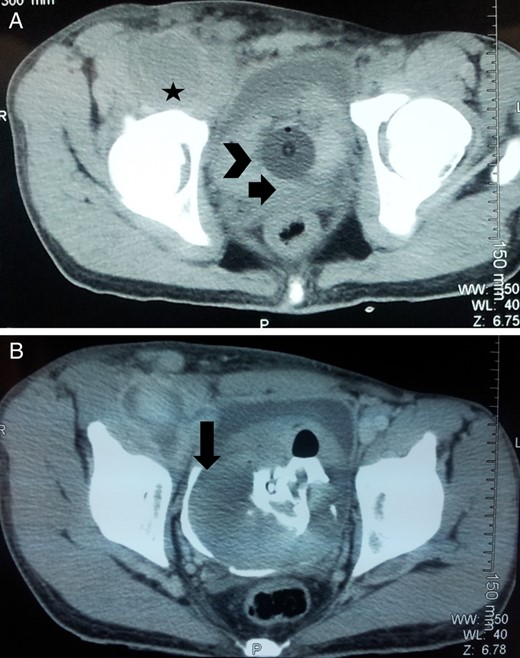

On contrast enhanced CT, a right common femoral pseudoaneurysm of size 12.5 × 6 × 6.5 cm was noted with intra-abdominal extension. Huge clot was also noted in the bladder with no obvious lesion in the kidney, ureter and bladder (Fig. 2). Thus, the patient was planned for exploration of pseudoaneurysm and urinary bladder. On exploration of right groin, there was a huge pseudoaneurysm in the groin extending above the inguinal ligament with 1 l of clot and blood (Fig. 3). Femoral artery was transected and proximal and distal ends were taken into control. Proximal end of femoral artery was ligated, and the leg was examined for distal saturation which was normal, so the distal end was also ligated. After addressing the femoral artery, the urinary bladder was explored. A small rent (∼0.5 × 0.5 cm) was noted in the right lateral wall of the bladder which was communicating with the wall of the pseudoaneurysm along with 2 l of blood and clot in the bladder. Thus, the enigma of hematuria was solved. Bladder was repaired according to standard technique and drain was kept in retroperitoneal space and abdomen was closed.

(A) Infected femoral pseudoaneurysm in an IV drug abuser; (B) intraoperative picture showing the communicating rent between pseudoaneurysm and bladder (marked by arrow).